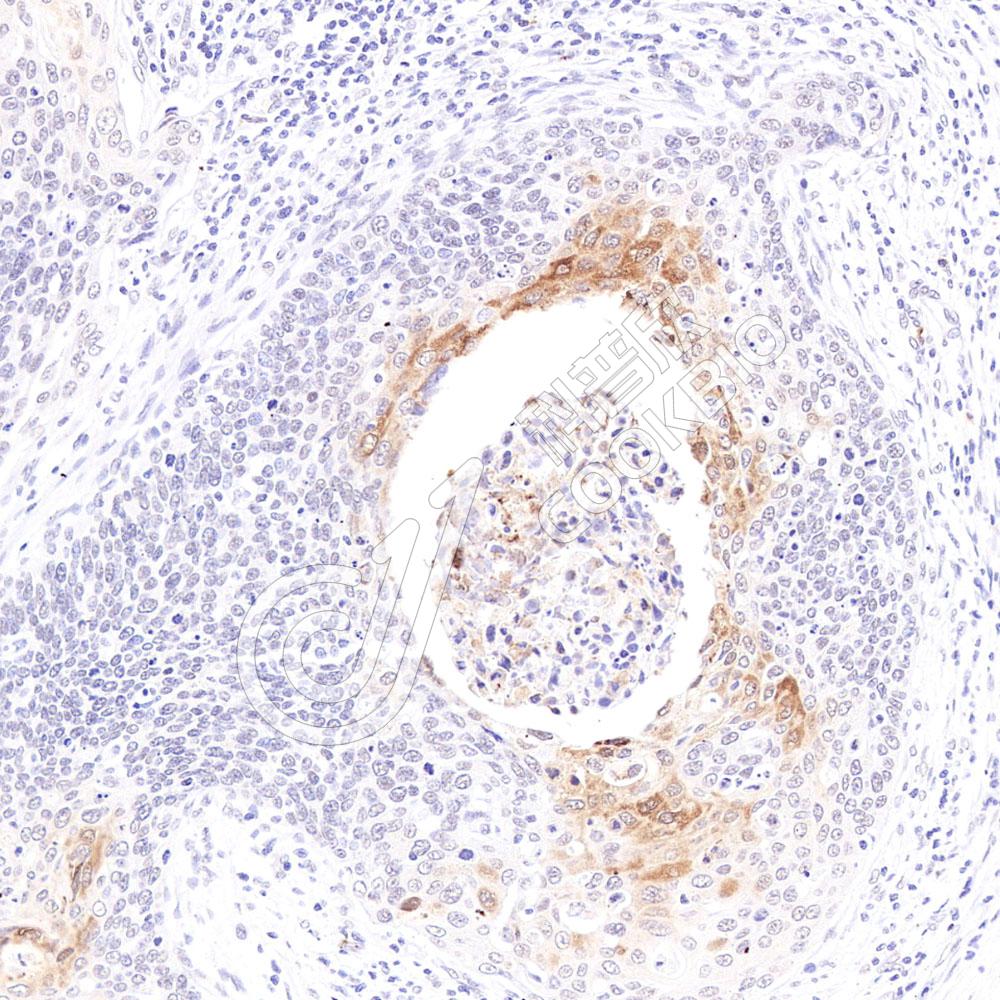

图像

WB检测Histone H3.

3蛋白(货号 K133078).

样品: 经RIPA裂解液(货号KSG2002)处理的蛋白质.

封闭: 3%脱脂牛奶(货号KSGC310001)溶于TBST溶液, 室温孵育1小时.

—抗: 1: 500稀释, 4℃ 孵育过夜.

二抗: HRP标记山羊抗兔IgG (H+L) (货号KB69909), 1: 5000稀释, 室温孵育1小时.